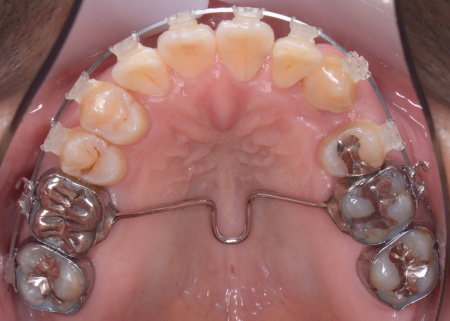

拝見したところ、上下の歯は、ずれたりねじれたりしてデコボコに生えており、著しく歯並びが乱れていました。

・上顎には歯の裏側に固定装置「トランスパラタルアーチ」を装着する

その後、上下の歯の表面にブラケットを接着し、上顎にはトランスパラタルアーチを、下顎にはミニインプラントを使用しながら、マルチブラケット矯正を開始しました。